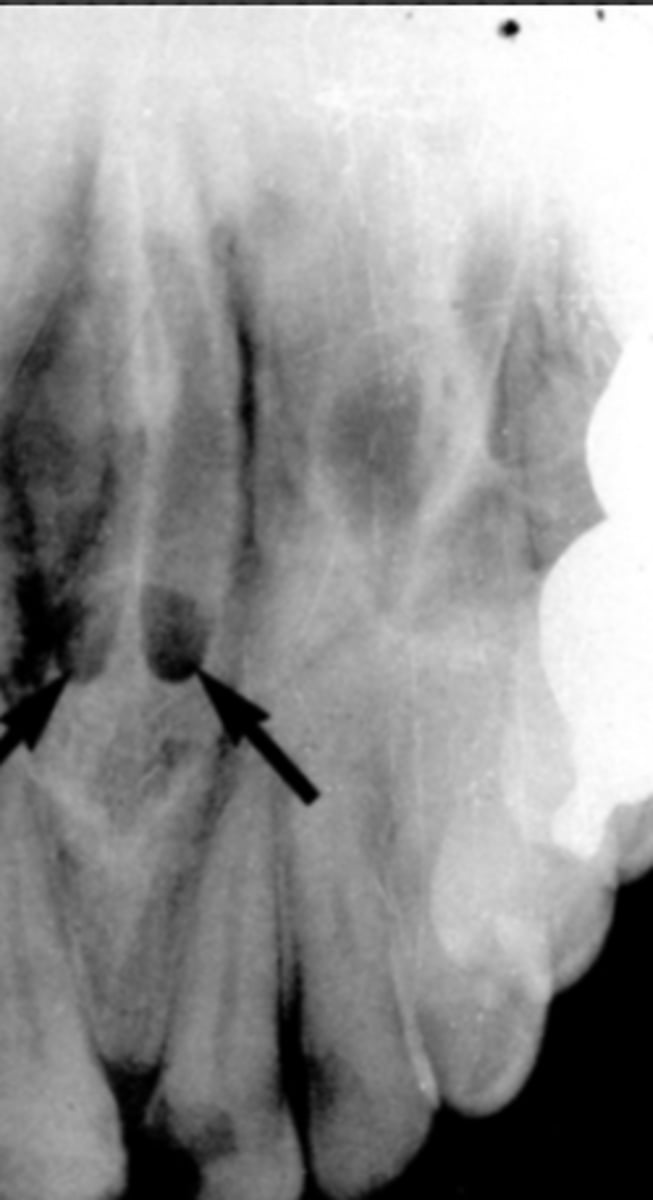

Black arrow - Nasal septum

White arrow- nasal conchae

Identify both structures

<p>Identify both structures</p>

Nasopalatine (incisive) foramen

Identify the round, ovoid radiolucent structure indicated by the black arrows.

<p>Identify the round, ovoid radiolucent structure indicated by the black arrows.</p>